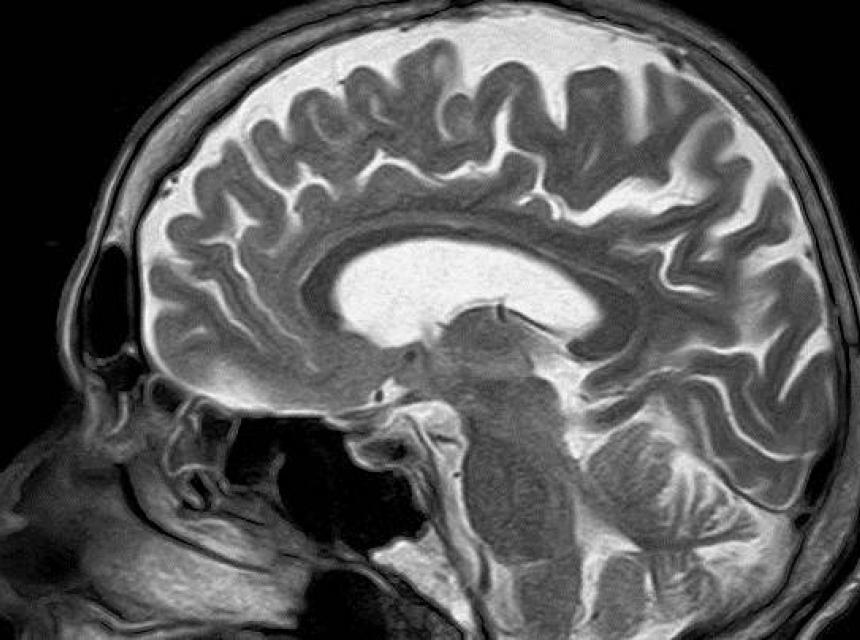

Mozak "punoljetan" tek sa 30 godina

Ljudski mozak postaje "punoljetan" tek sa 30 godina, odnosno sazrijeva sporije, navode naučnici sa univerziteta Oxford i Cambridge.

Prelazak mozga iz djetinjstva u odraslo doba odvija se tokom tri decenije, pa mozak do tridesete godine nije u potpunosti razvijen.